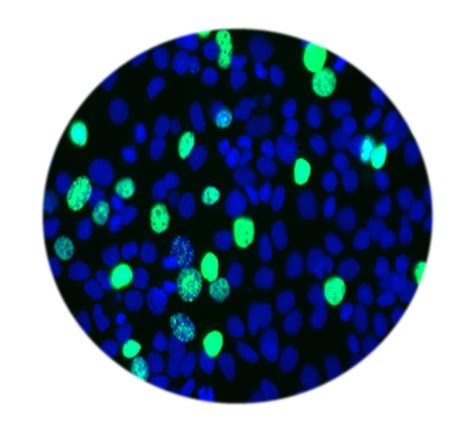

640×640

researchgate.net

Flow cytometry analysis of cell cycle and proliferatio…

baseclick.eu

EdU Cell Proliferation Assay for Flow Cytometry